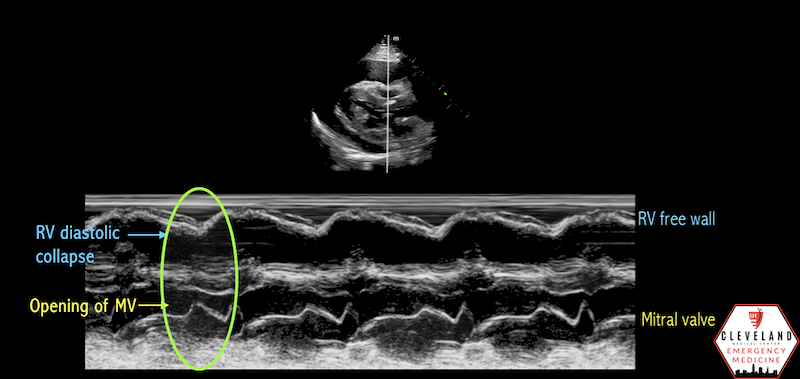

Cardiac tamponade

What condition is seen in the following m-mode image?